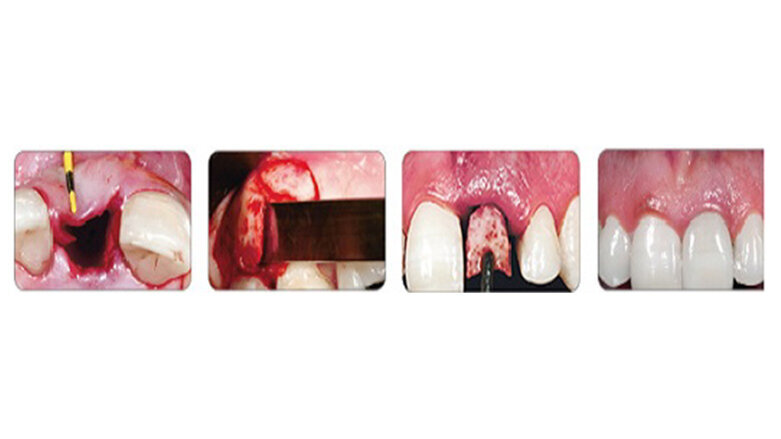

Η τεχνική IDR - Άμεσης οδοντοφατνιακής Αποκατάστασης έχει αναπτυχθεί και χρησιμοποιείται εδώ και 11 χρόνια. Στην τεχνική αυτή η επιλογή της κατάλληλης σμίλης για την αφαίρεση του μοσχεύματος από το οπισθογόμφιο όγκωμα της άνω γνάθου γίνεται σύμφωνα με το σχήμα του υπάρχοντος ελλείμματος στην περιοχή υποδοχής και τον απαιτούμενο οστικό όγκο.

Η τεχνική IDR - Άμεσης οδοντοφατνιακής Αποκατάστασης έχει αναπτυχθεί και χρησιμοποιείται εδώ και 11 χρόνια. Στην τεχνική αυτή η επιλογή της κατάλληλης σμίλης για την αφαίρεση του μοσχεύματος από το οπισθογόμφιο όγκωμα της άνω γνάθου γίνεται σύμφωνα με το σχήμα του υπάρχοντος ελλείμματος στην περιοχή υποδοχής και τον απαιτούμενο οστικό όγκο. Η αποκατάσταση/αύξηση της ιστικής απώλειας γίνεται στο ίδιο χειρουργείο με αυτό της τοποθέτησης εμφυτεύματος.

Τα πιο κατάλληλα σχήματα σμιλών είναι τα ευθεία και με διαμέτρους 6, 8 ή 10 mm εύρους. Ως γενικός κανόνας ισχύει ότι η επιλεγόμενη σμίλη θα πρέπει να είναι 2 mm ευρύτερη από το εύρος του μοσχεύματος που θα αφαιρεθεί.

Αυτές οι σμίλες έχουν ένα μετρημένο σε χιλιοστά ενεργό άκρο, με σκοπό να διευκολύνουν τη μέτρηση του μοσχεύματος τη στιγμή της αφαίρεσής του, επιτρέποντας την συλλογή του οστικού δείγματος με το κατάλληλο μήκος και πάχος.